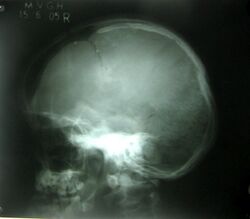

An obvious fracture to the crown of the skull causing damage to the brain.

Fractures

Bone fractures to the crown of the head are linear or depressed and range in severity based on the impact to the skull. The linear fracture involves a break to the skull whereas the depressed fracture results in the scatter of skull fragments.[19] The skull fractures are mainly caused by incidents involving a vehicle, assault, or a fall. In more severe cases, penetrating skull fractures are caused by an object such as a metal rod or bullet breaking through the skull completely. Based on the severity of the fracture, symptoms may include nausea, memory loss, concussion, bruise, and lethargy. Another symptom such as bleeding results in the build-up of pressure in the skull since it is an enclosed cavity and thus pushes the brain to the brainstem opening leading to a coma.[20] Diagnosis occurs due to a range of physical exams which identifies the extent of the injury and possible treatments. For example, the computerised tomography scan identifies the site of the fracture and any associated injuries to the brain, whereas magnetic resonance imaging highlights the damaged tissue. The treatments of severe skull fractures include surgery and medication to avoid infection, however, for linear fractures treatment involves rest for approximately 5 to 10 days, so that the crown can heal.[21]